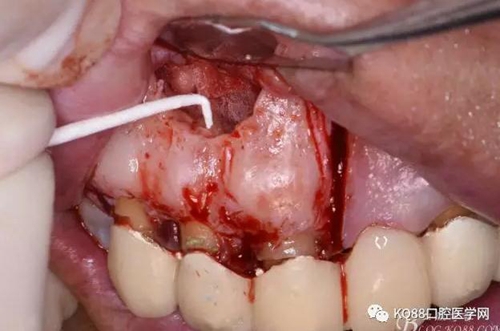

圖7. 分別在13的遠(yuǎn)中和11的近中做垂直切口加齦溝內(nèi)水平切口,形成梯形瓣

圖8.翻開梯形瓣

圖9.去除唇側(cè)薄的骨壁,暴露出囊壁